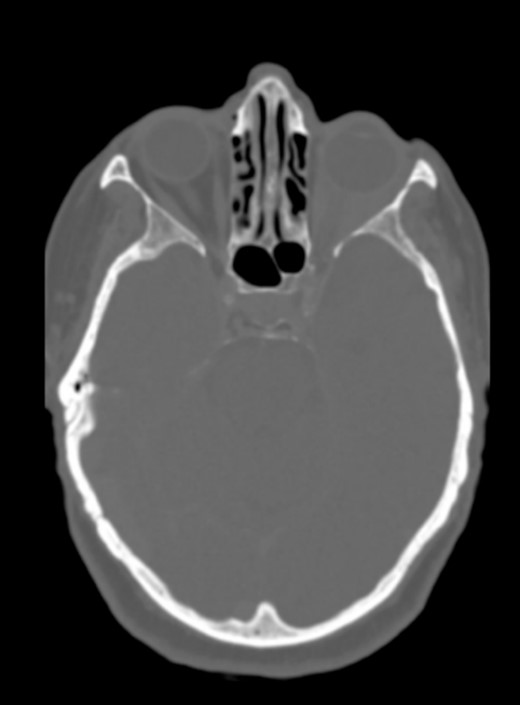

There was no evidence of involvement of the central nervous system, and no cranial bone lesions were detected in the CT scan (Fig. 3).